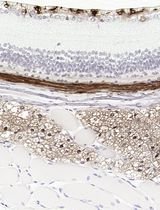

Although it is possible to use a tartrate-resistant acid phosphatase (TRAP) stain to assist in identifying osteoclasts, a separate method is needed to determine the bone resorption activity of osteoclasts. Since osteoclasts leave “pits” after bone matrix resorption (Charles et al., 2014), it is possible to stain pits as a method of measuring osteoclast bone resorption activity. The pit assay protocol enables researchers to stain bony slices that were co-cultured with osteoclasts with toluidine blue in order to allow the visualization, capture, and analysis of osteoclast resorptive activity based on the number, size and depth of pits (Zhou et al., 2015). The pit assay protocol is separated into three sequential stages: Preparation of bone slices (1); preparation of osteoclast precursors (Ross et al., 2006; Teitelbaum et al., 2000) (2), and bone resorption pit assay (3).